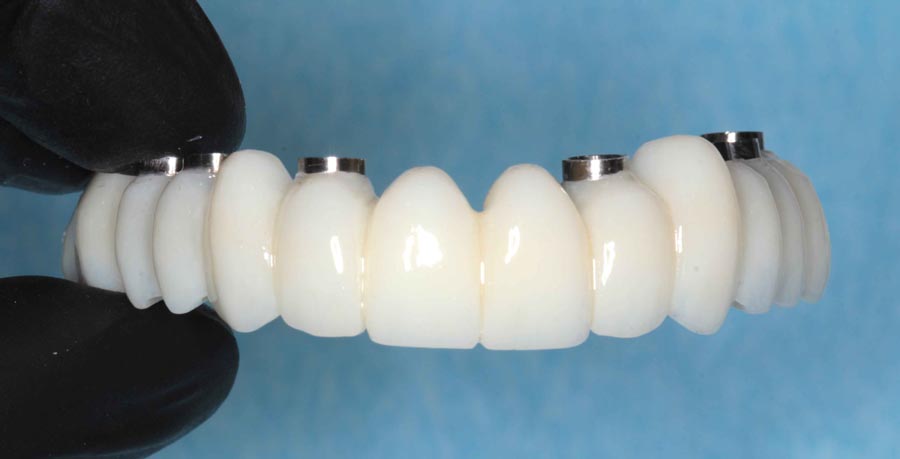

Prototype wax-up, frontal. Any imperfections or patient requests are changed in this prototype stage.